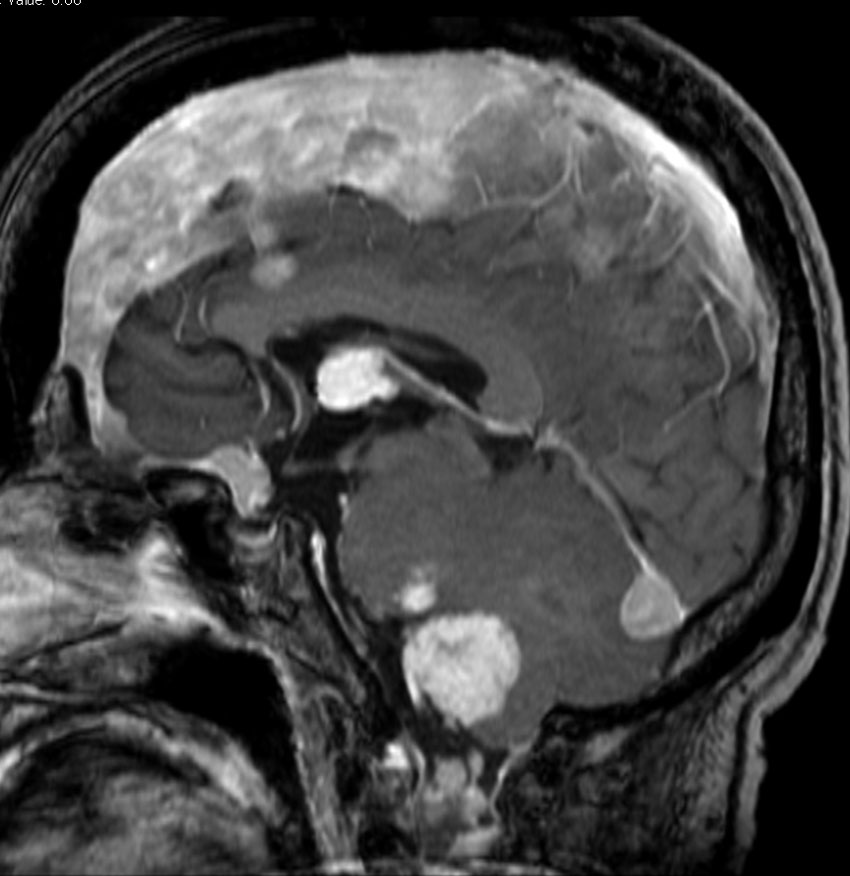

NF-2で脳腫瘍と間違っていはいけない大脳の病変

- NF-1よりずっと少ないのですが,NF-2でも大脳の病変はしばしばみられます

- MRIでグリオーマのようにみえますがそうではありません。T2強調画像で白く見えてガドリニウム造影されないのが一般的な特徴です

- 微小過誤腫 (microhamartoma)とか皮質異形成 (cortical dysplasia)とか血管周囲腔拡大 (Virchow-Robin space enlargement)とかいわれるものです

左側の病変はおそらく皮質異形成 cortical dysplasiaで,右中央寄りの病変はVirchow-Robin spaceの拡大です。

病理はとれないので確定できませんが,おそらく微小過誤腫 microhamartomaなのでしょう